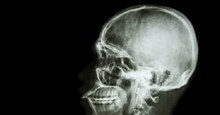

Để có được kết quả này, 10 bệnh nhân trước hết được kiểm tra lâm sàng đầy đủ về sức khỏe đặc biệt là chất lượng cũng như tình trạng hoạt động sinh học giữa sụn khớp gối và sụn mũi.

Sau đó, bác sỹ Martin và các đồng nghiệp lấy một mẫu nhỏ các tế bào sụn từ xương mũi của bệnh nhân, sau đó nuôi chúng trong môi trường chứa hormone tăng trưởng liên tục trong suốt trong hai tuần. Tất cả các tế bào sụn mũi này được đặt trong một màng collagen và nuôi cấy tiếp tục trong hai tuần nữa.

Kế tiếp, toàn bộ phần sụn được tách, sau khi nuôi cấy được cấy ghép thẳng vào phần sụn khớp bị hỏng do chấn thương gây ra trên cơ thể bệnh nhân.

Kết thúc quá trình hậu phẫu, bệnh nhân được theo dõi suốt 6 đến 8 tuần, và có thể mất hơn vài tháng mới cho sụn khớp gối dụng nạp và phục hồi bình thường.

Hai năm sau, 10 người này đã được chụp MRI khớp gối lần nữa cho thấy các mô sụn khớp gối làm từ sụn mũi đã phát triển thành mô mới, hoạt động bình thường, đầu gối của 9/10 người hoạt động linh hoạt hơn, bớt tình trạng đau hơn.